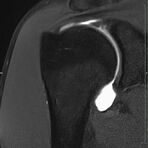

Gelenke

• Beurteilung von Knochen, Bändern und anderen Weichteilstrukturen der Gelenke nach Unfall.

• Arthrosediagnostik (Knorpelschaden)

• Impingement-Symptomatik

• Ursachenklärung bei wiederholter spontaner Gelenkluxation

• Ausbreitungsdiagnostik bei Gelenkentzündung, z.B. im Rahmen von rheumatischen Grunderkrankungen

Arthrographie

• MR-Arthrographie – nach örtlicher Betäubung und gründlicher Desinfektion der Haut wird unter Lagekontrolle mit Röntgen-Durchleuchtung eine kleine Nadel in den Gelenkraum positoniert und darüber ein MR-taugliches Kontrastmittel in den Gelenkraum gespritzt. Danach wird die Nadel entfernt. Anschließend erfolgt die MRT des Gelenkes. Diese Methode stellt kleine anatomische Strukturen des Gelenkraumes verbessert dar, z.B. zur Therapieplanung vor Arthroskopie bei Sportverletzungen der Schulter oder Gelenkinstabilität.